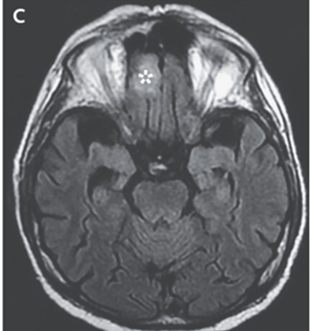

頭部MRIでは右眼窩、両側の上顎洞と篩骨洞、および右前頭葉に高信号領域を認めた。